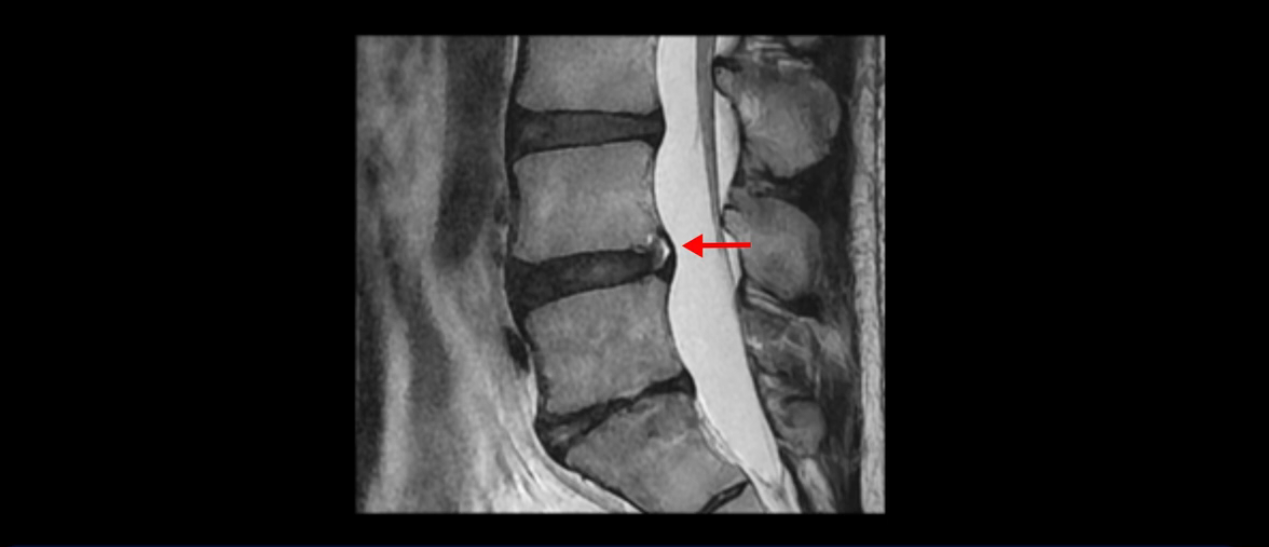

우선 이분 MRI를 보면 허리 모든 마디의 디스크가 퇴행되어 있고

여러 마디의 디스크가 조금씩 밀려나와 보이고, 디스크 섬유륜도 찢어져 보이는 마디도 보입니다.

그런데 이분의 증상과 MRI가 전혀 일치하지 않는데, 왜 그런지 지금부터 자세히 설명드립니다. 이분 증상은 앉으면 엉치와 허리가 심하게 아파 10분 이상 앉는 게 어렵고 양쪽 발가락이 앉아있을 때나 누워있을 때 다 저립니다. 걸을 때도 아파서 10분 걷기도 어렵습니다. MRI를 마디마디 살펴보면 1번 2번은 오른쪽으로 살짝 밀려나온 디스크가 있지만 전혀 심하지 않고, 뒤에 또 설명하겠지만 최근에 밀려나온 급성 디스크가 아니고 오래된 디스크로 판단됩니다.

4번 5번은 가운데로 섬유륜이 찢어져서 디스크가 살짝 밀려나와 있지만 역시나 최근에 찢어지고 밀려나온 걸로 판단되지 않고 오래 전에 찢어진 흔적으로 보입니다.

이분은 어떤 한 병원에서 디스크 내장증 얘기를 들으셨는데요. 여기 보시는 것처럼 4번 5번의 하얀 HIZ(High Intensity Zone)을 보고 디스크 내장증의 근거로 얘기하는 병원들이 있는데,

이 HIZ는 섬유륜이 찢어졌다가 이미 아문 뒤에도 얼마든지 보일 수 있는 흔적일 가능성이 있어서 재채기를 하면 아픈지, 허리를 구부릴 때 날카로운 통증이 생기는가 등의 증상으로 구별해야 하는데 MRI만 보고 HIZ가 보이면 그게 마치 통증의 원인인 것처럼 얘기하는 의사들이 있습니다. 이분 MRI를 자세히 보고 증상을 정말 자세히 들어본 의사가 있었더라면 다른 환자분들처럼 증상과 MRI가 일치하지 않는다는 얘기를 들을 수 있었을 텐데 이분은 그런 얘기는 듣지 못했습니다.